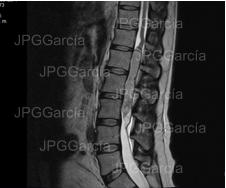

Estudio de resonancia magnética prequirúrgico que demuestra

una lesión tumoral torácica relacionada a un meningioma

RESECCIÓN MICROQUIRÚRGICA DE MENINGIOMA TORÁCICO

Estudio de resonancia magnética prequirúrgico que demuestra una lesión tumoral torácica relacionada a un meningioma